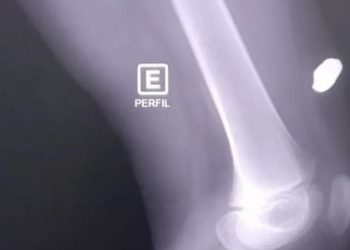

Bala perdida atravessa parede a acerta perna de menino que dormia em casa no Amazonas

AMAZONAS - Uma mãe acordou com barulho de tiro em Itacoatiara e encontrou o filho sangrando com uma bala perdida ...